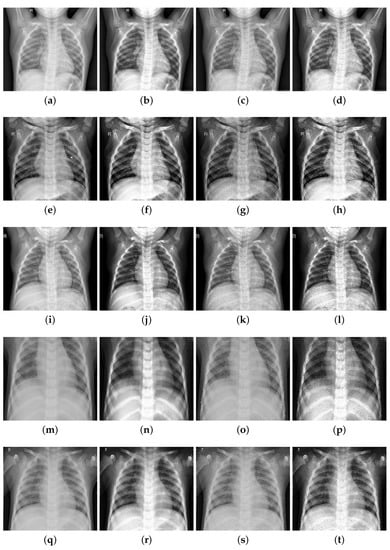

In order to test the effectiveness of image enhancement methods, this paper uses the methods of contrast enhancement and edge coefficient enhancement to enhance the athlete lung medical images. Five medical images were taken as examples (1, 2, 3 without pneumonia; 4, 5 with pneumonia) and image enhancement was performed on these five images. The original images, the images with enhanced contrast, the images with enhanced edge information, and the images with integrated enhancement are shown in Figure 8.

Figure 8. Image enhancement effect comparison image: (a) original-1; (b) contrast boost-1; (c) enhanced edge-1; (d) integrated-1; (e) original-2; (f) contrast boost-2; (g) enhanced edge-2; (h) integrated-2; (i) original-3; (j) contrast boost-3; (k) enhanced edge-3; (l) integrated-3; (m) original-4; (n) contrast boost-4; (o) enhanced edge-4; (p) integrated-4; (q) original-5; (r) contrast boost-5; (s) enhanced edge-5; (t) integrated-5.